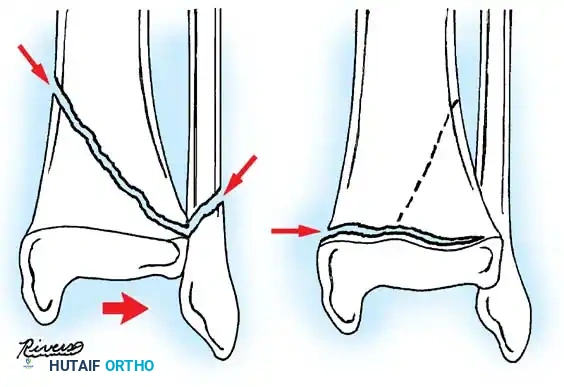

Fig. 33-173: Salter-Harris type I and II fractures with posterior displacement of the tibial shaft may severely injure the popliteal artery.

- Type I and II Fractures: Most can be managed with closed reduction and a bent-knee cast. However, posterior displacement requires meticulous reduction to relieve arterial tension. Unacceptable angulation must be corrected; malunion in older children will not remodel sufficiently.

- Type III Fractures: These present in two distinct patterns:

- An intra-articular fracture analogous to an adult tibial plateau fracture.

- A fracture propagating through the tibial tuberosity physis, extending proximally across the epiphysis and into the knee joint.

Fig. 33-174: Salter-Harris type III fracture of the proximal tibia. A, Fracture analogous to a tibial plateau fracture. B, Fracture through the tibial tuberosity and across the epiphysis into the knee joint.

These tuberosity-extending fractures are not simple avulsions; they are massive, tongue-type Salter-Harris III injuries that lift the entire tibial tuberosity and anterior proximal physis superiorly. They almost universally necessitate open reduction and internal fixation (ORIF) to restore joint congruity and extensor mechanism continuity.